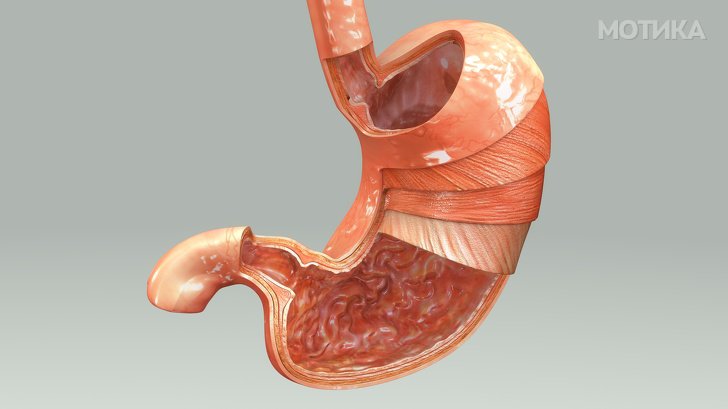

8. Желудник

- Желудникот има доста капацитет за складирање, и може да го промени својот волумен од 1 литар до 4 литри во зависност од тоа колку е полн.

- Неговата киселина е толку силна што може да ја раствори не само вашата вечера туку и некои метали.

- За да се заштити од „само-варење“, стомакот има неколку слоеви, секој од нив игра критична улога, а на секои 2 недели малиот слој на обвивката целосно се регенерира.

- На празен стомак, киселоста на желудечните сокови е толку висока што може да ја раствори синтетичката пластика.